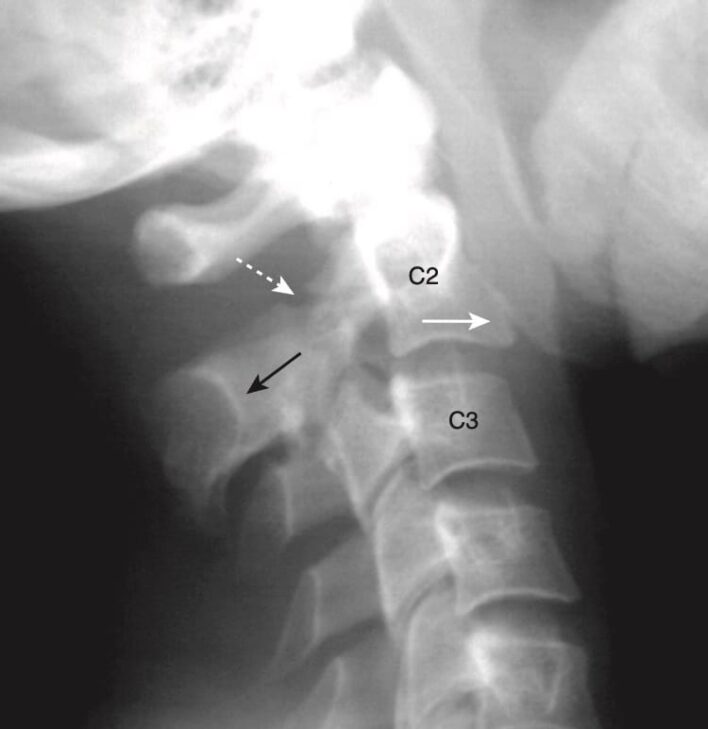

- Trên phim chụp X quang thường quy, dấu hiệu của gãy Jefferson là lệch bù ra ngoài hai bên của các khối bên của C1 so với C2 quan sát được trên phim X quang cột sống cổ tư thế thẳng và há/mở miệng (open-mouth view) (góc nhìn đội trục). Gãy xương được khẳng định bằng chụp CT (Hình 15).

- Gãy xương Jefferson là gãy xương “tự giảm áp” (self-decompressing), trong đó ống sống ở ngang mức gãy xương đủ rộng để dung chứa bất kỳ sự sưng phù nào của tuỷ sống. Thường không có khiếm khuyết thần kinh liên quan đến loại gãy xương này.